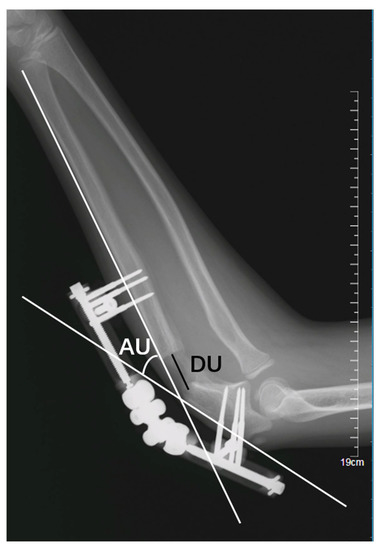

- Lengthening distance of the ulna (DU): the distance, in millimetres (mm), between the proximal and distal fragments of the fractured ulna (Figure 3); and

- (2)

- Angulation of the ulna (AU): the angle, in degrees, between the line passing at the level of posterior cortex of the proximal and the distal fragment of the fractured ulna (Figure 3);